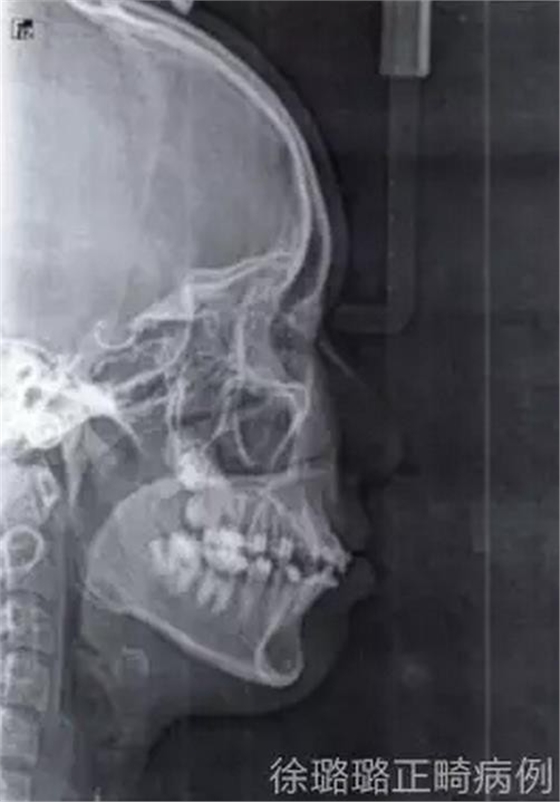

面部分析:面部左右對稱、和諧;凹面型得到改善。

咬合分析:建立了雙側(cè)磨牙及尖牙 I 類關(guān)系;前牙覆牙合、覆蓋關(guān)系正常;上下中線基本與面中線一致。